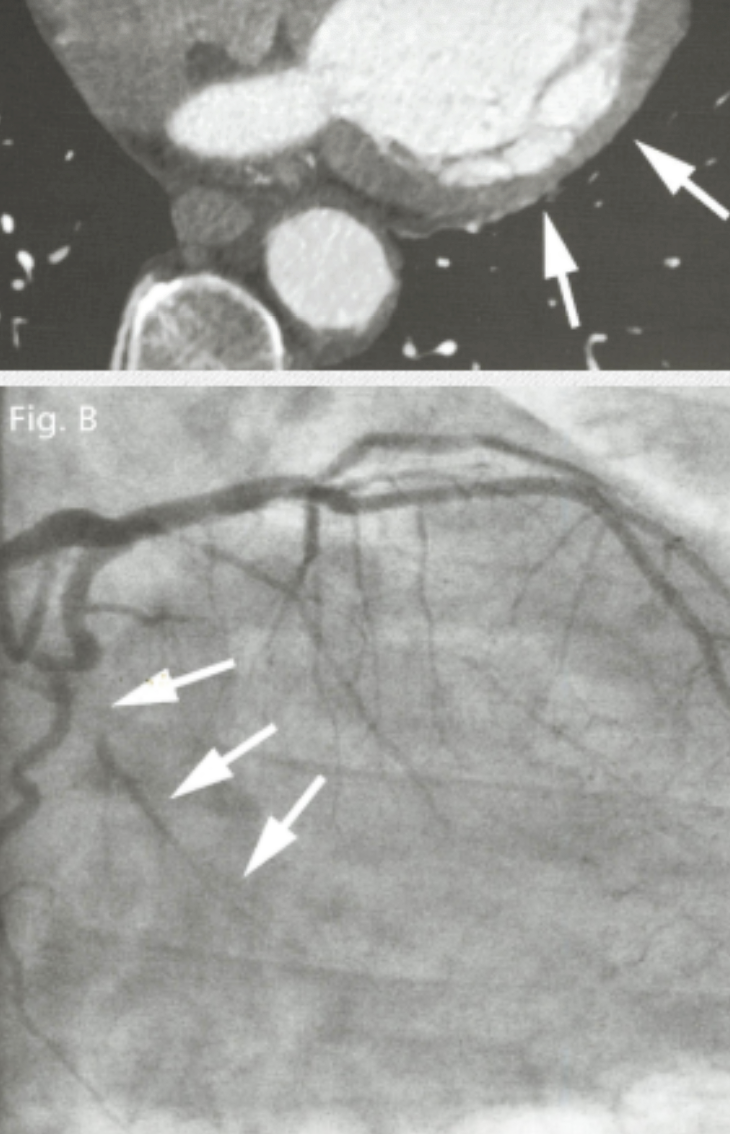

What type of post-processing methods were used to generate the reformatted image shown below?

Multiplanar reformatting and thin slab MIP (5 mm)

Describe the findings and most likely finding on coronary angiorgram

Occlusion in LCFx territory